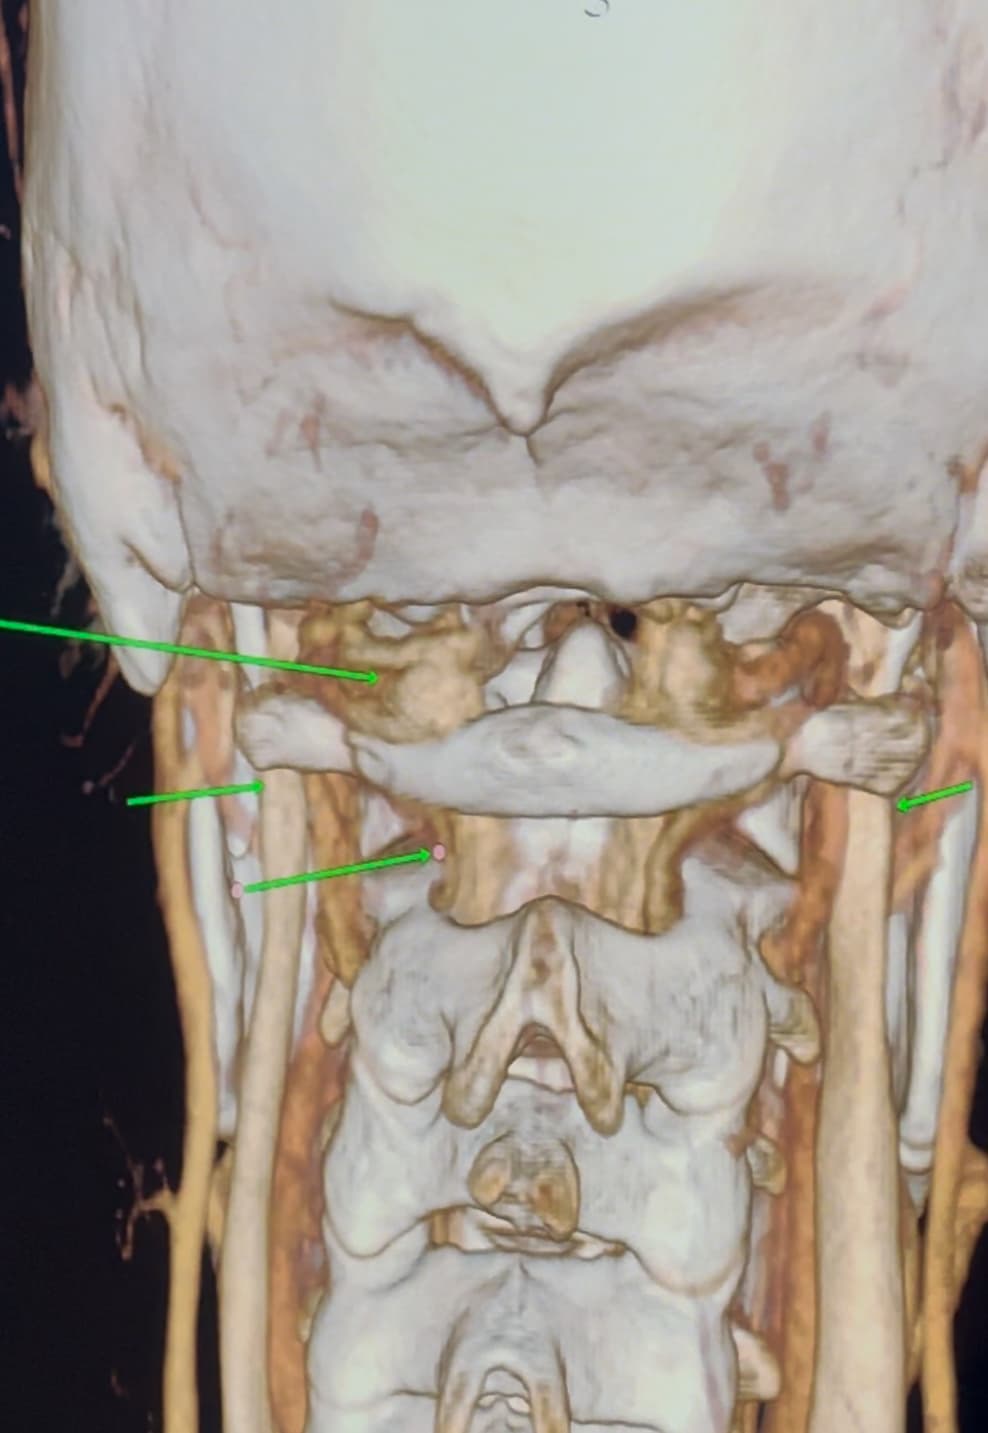

I have a cbct and CVA made wich shows elongated styloids and calcified stylohoids around 5 cm. Space left in neutral position between c1 is 3.5mm. Left IJV compression in laying position but there seems to be mainly some soft tissue compression there. So not due to compression of c1/styloid. The right is my dominant IJV.

Hi Rob & welcome! Looking at your CT, & obviously we’re not experts, I would estimate that your styloid & calcified ligament section is longer than 5 cm; on your left in the middle image it goes way past your C2 vertebra! We have found that the measurements from CTs are often wrong as it can be quite hard to measure accurately due to CT imaging being done in slices…

The IJVs do collapse naturally when flat, so it could be due to that, in your 3rd image it looks like the IJV is flattened higher up, so what would be right by the skull base. It could be like that naturally because of being flat for the CT, or it could be that it is being compressed where it emerges from the skull at the jugular foramen - if styloids are quite thick that is possible, & yours do look a little wide at the top… It looks like there could be something pinching the IJV between it & the styloid where you’ve marked too; we’ve had members who’ve had compression from an enlarged SCM muscle, the digastric muscle, omahyoid muscle, as well as other blood vessels & nerves… I’d guess where the compression is that the digastric muscle would be the most likely if it was a muscle, or maybe the stylohyoid muscle, although we don’t hear much about that one!

@Rob12345 - Welcome to our forum! I have nothing to add to what @Jules said, but did want to say WOW! You do have very long styloids. The “kink” in your ICA (internal carotid) isn’t really a kink more of a curve, but I can see based on the image, that it could be causing some slowed or backed up blood flow going into your brain. The IJV compression is curious as it appears to be more than the styloid causing the problem but clearly C1 seems not to be involved. I think Jules has made some logical assumptions regarding other possible compression culprits.

@Rob12345 - I can see you have bilateral IJV compression in the images you’ve posted & it’s possible the middle image in your first set of pictures is pointing to collateral veins. I’m not great at identifying collaterals, but I can say for sure your IJVs are being squashed between your styloids & C1.